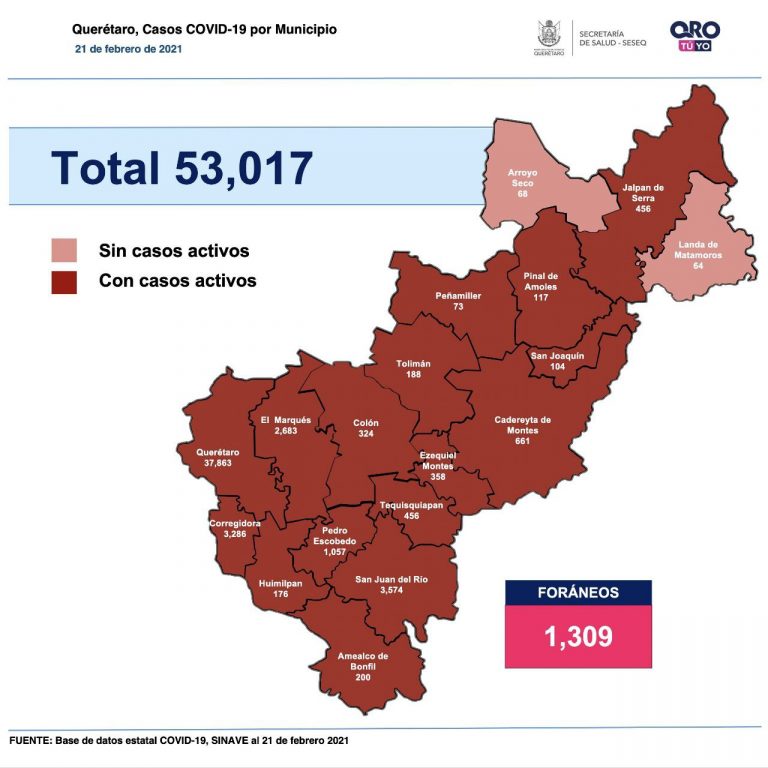

Se suman 227 casos de Covid-19 en Querétaro